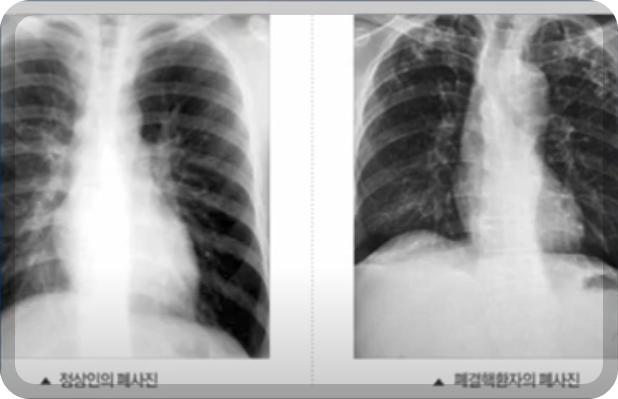

⯄ 식품 및 음식점 그리고 학교급식 보건증 검사에는 폐결핵 흉부 Xㅡray.